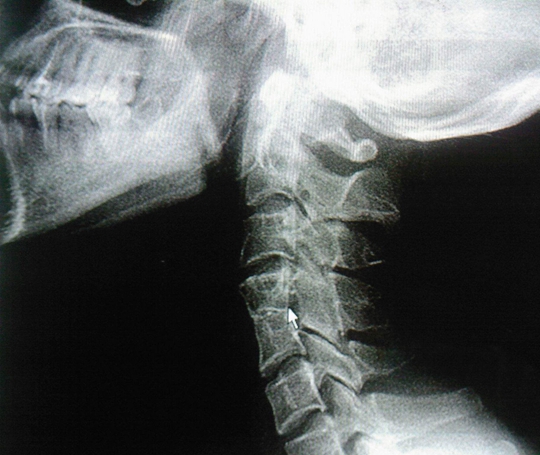

隨著社會(huì)競(jìng)爭(zhēng)壓力增大,白領(lǐng)人士們天天坐在辦公桌前,敲著電腦,經(jīng)常保持同一個(gè)姿勢(shì)很久不動(dòng)。而且手機(jī)普及,年青一代手機(jī)不離手,恨不得吃飯的時(shí)候也在看手機(jī),這些都促成了頸椎病的發(fā)生。頸椎病的癥狀并不是簡(jiǎn)單的疼痛,有可能會(huì)直接眩暈,猝倒,甚至引起下肢癱瘓。目前治療方法大同小異,今天小編就來(lái)給大家介紹幾種日本治療頸椎病的方法,希望對(duì)大家有所幫助。并且日本有一種膏藥對(duì)頸椎治效果果特別棒,我們一起來(lái)看看日本治療頸椎病的方法吧。